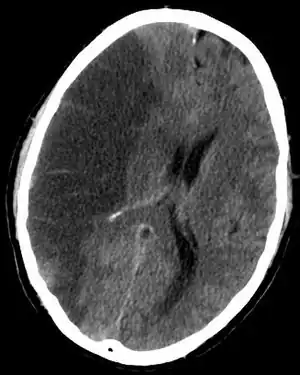

Imagerie cérébrale

Elle permet de voir l'accident vasculaire, de le dater en partie, d'en connaître le mécanisme, d'éliminer d'autres maladies pouvant être responsable de l'accident déficitaire.

Le scanner crânien est fait, sauf contre-indication, avec injection d'un produit de contraste iodé. Si l'accident est ischémique, il permet de visualiser la topographie, l'étendue et le nombre de lésions. S'il est hémorragique, il en fait le diagnostic.

L'imagerie par résonance magnétique crânienne, faite également après injection d'un produit de contraste, donne le même type de renseignements mais est plus sensible si l'accident est très récent. Elle peut être complétée dans la même séance par une angio-IRM permettant de visualiser les grands axes vasculaires extra et intracrâniens.